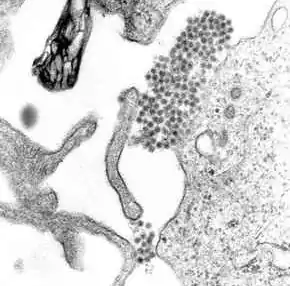

A TEM micrograph showing dengue virus virions (the cluster of dark dots near the center)